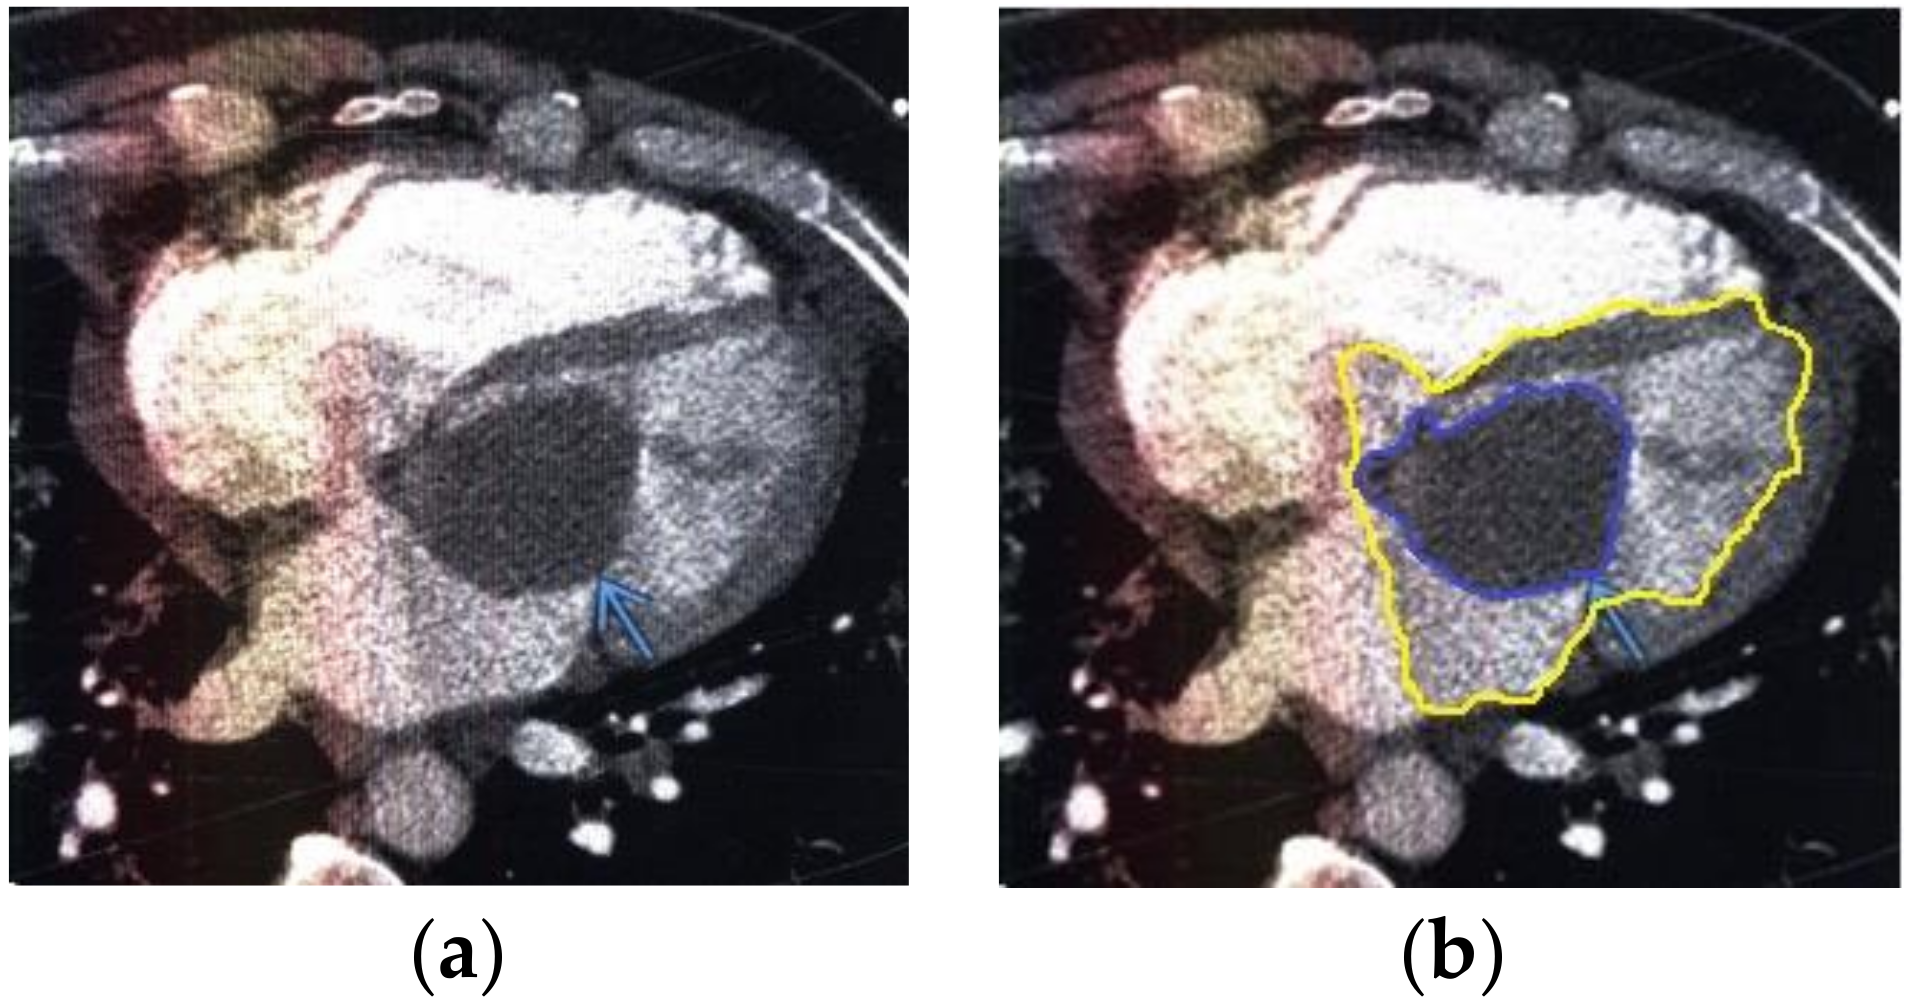

The contour extraction method was used to identify cancerous areas that, after applying the model to eliminate mixed noise, had an increased contrast of volumetric heterogeneous formations in the region of the heart [27]. This method was developed by the authors when analyzing thermal images to assess the condition of the coronary vessels of the myocardium under cardiopulmonary bypass. The contours of the cancerous regions in the examples used for applying the model to eliminate mixed noise (Figure 4, Figure 5, Figure 6, Figure 7, Figure 8 and Figure 9) are highlighted in yellow and they represent the visual boundary of the distribution of volumetric heterogeneous formations.

• For a patient with a history of melanoma: during MRI with contrast enhancement, a volumetric formation adjacent to the atrial septum was visualized in the left atrium (Figure 5).

Figure 5. Heart MRI: (a) image with white noise and (b) denoised image with contrast enhancement of volume melanoma in the left atrium.